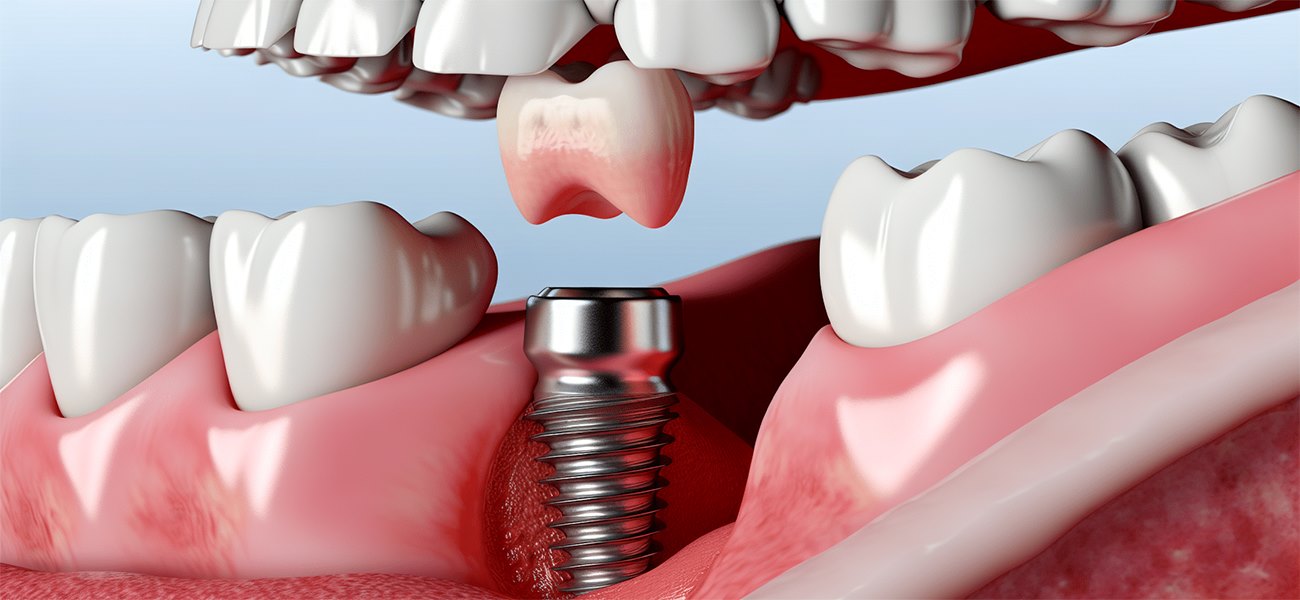

ایمپلنت دندان یک ریشه مصنوعی است که در استخوان فک قرار میگیرد و به عنوان پایهای برای قرار دادن دندانهای مصنوعی عمل میکند. این روش به بیماران کمک میکند تا عملکرد طبیعی دندانها را بازگردانند و از نظر زیبایی نیز ظاهر بهتری داشته باشند.

- جراحی ایمپلنت

پس از جراحی، بیمار باید دورهای را برای بهبودی سپری کند. در این مدت، استخوان فک به ایمپلنت جوش میخورد و پایهای محکم برای دندان مصنوعی فراهم میشود. این دوره معمولاً چند ماه طول میکشد.

- قرار دادن پروتز

پس از اتمام دوره بهبودی، پروتز یا دندان مصنوعی روی ایمپلنت قرار داده میشود. این مرحله معمولاً بدون درد است و بیمار میتواند بلافاصله پس از آن از دندانهای جدید خود استفاده کند.